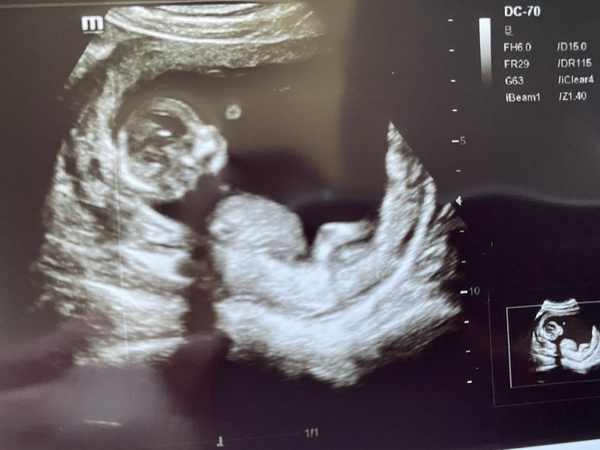

Hi there, would anyone be able to tell by my 12 week scan whether I'm having a boy or girl? Based on the skull theory?

@Cherrychops100 here’s my little boy 💙 I was 12+6 when I had my scan

@Melbs6 and according to the skull theory, I would say his little head is very round and girl-like, especially his chin. I'm hoping for a little girl, of course I won't mind but it's a little preference, everyone on Facebook has said boy and I cannot wait for the scan, it's on the 17th of April Grin

I’m going to say girl as it looks similar to ours and we are having a little girl ! Congrats either way x

@Cherrychops100 yeah according to skull theory he has a textbook girl skull 😂 tbh I did hope for a little girl but now I know he’s a boy I’m really happy. The most important thing is that the baby is healthy at the end of the day. I’m due on the 21st August and my anomaly scan is on the 6th April (I had a private gender scan). When are you due? I can imagine we’ll be pretty close